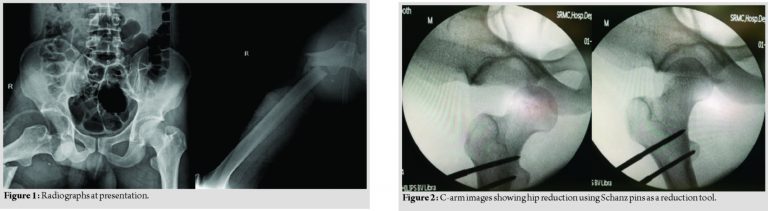

A 26-year-old male, a young adult who is a welder by occupation, was brought on new year’s eve of 2017 to the emergency room following a history of RTA when he fell over from his motorbike as he was about to crash into a stationary vehicle and sustained injury to his right thigh, he was brought within 2 h after sustaining trauma and complained of severe pain over his right hip and inability to move his right lower limb. On examination, he was conscious and oriented, hemodynamically stable, and unable to move his right lower limb which was externally rotated and shortened with a diffusely swollen upper thigh. He had tenderness over the right groin area with a palpable lump. Distal neurovascular examination was normal. Radiographic evaluation of pelvis and right thigh revealed right hip anterior dislocation with ipsilateral subtrochanteric femur fracture (Fig. 1).

The patient was worked up for surgery immediately and emergency surgical intervention to reduce the hip was planned. After inducing anesthesia, no attempts of closed reduction using the various techniques to reduce the anterior dislocation were tried as the patient had an ipsilateral femur fracture because all the forces pass through the fracture site. Therefore, the patient was placed on a radiolucent table and with a help of image intensifier, under strict sterile precaution, initially, one 5 mm Schanz pin was placed close to the intertrochanteric region and used as a joystick to reduce the head into the acetabulum but was unsuccessful; hence, another Schanz pin was placed parallelly and connected with each other using a pin to rod connector and then the rod along with the pins was used as an external reduction tool to reduce the right hip in a closed manner without the need of open reduction, thereby reducing the chances of vascular insult on the capsule. The closed reduction was found to be satisfactory as checked under the image intensifier (Fig. 2) and further reduction of the subtrochanteric region was done and a uniplanar external fixator was applied as a temporary procedure. This emergency procedure was done within 6 h of the insult. After 2 days, the patient was taken up for definitive procedure in the form of external fixator removal and closed reduction and intramedullary interlocking nailing using a cephalomedullary nail but used as IMIL nail (Fig. 3) with the patient placed on a fracture table under C-arm guidance. Postoperatively, regular wound inspections and dressings were done and wound was found to be healthy.